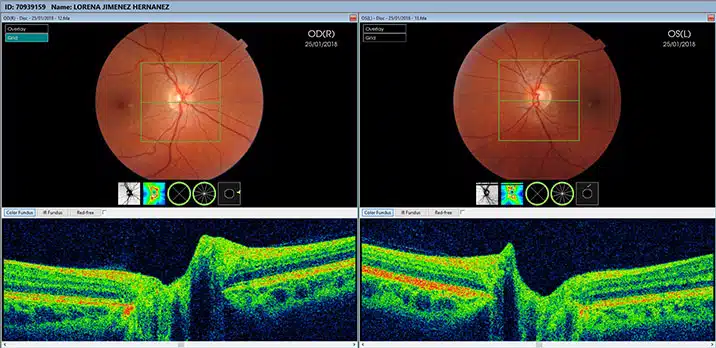

La tomografía de coherencia óptica (OCT, por sus siglas en inglés) es una herramienta diagnóstica esencial en la oftalmología moderna, permitiendo evaluar de manera no invasiva las estructuras del ojo, especialmente la retina. La interpretación precisa de las imágenes de OCT es crucial para el diagnóstico y manejo de diversas patologías oculares. Este artículo proporciona una guía completa sobre la interpretación de OCT en la práctica clínica, incluyendo aspectos clave, herramientas de análisis de software, casos clínicos comunes, factores a considerar en la evaluación y recomendaciones para su uso.

- Anatomía Normal y Patológica: Conocer la anatomía normal de la retina y las capas oculares es esencial. Familiarizarse con las características de cada capa de la retina, como la capa de fibras nerviosas, la capa de células ganglionares, y la capa de los fotorreceptores, facilita la identificación de anomalías.

- Patrones de Enfermedad: Distintas patologías tienen patrones específicos en las imágenes de OCT. Por ejemplo, el edema macularEl edema macular es una acumulación de líquido en la mácula, la parte central de la retina, lo que provoca una visión borrosa o distorsionada. Esta condición puede ser consecuencia de diversas enfermedades, como la diabetes o la retinopatía. El diagnóstico temprano y el tratamiento adecuado son fundamentales para prevenir daños permanentes en la visión. Entre los tratamientos disponibles se encuentran la terapia con láser y medicamentos antiinflamatorios.... más puede presentarse como engrosamiento de la retina, mientras que en el caso de la degeneración macular asociada a la edad (DMAE), se pueden observar drusas y cambios en la pigmentación.

- Segmentación Automática: Muchos sistemas de OCT modernos utilizan algoritmos de segmentación automática que identifican y etiquetan las diferentes capas de la retina, facilitando su análisis.

- Análisis Cuantitativo: Herramientas que permiten la medición cuantitativa de las capas retinianas son valiosas para monitorizar cambios en el grosor de la retina a lo largo del tiempo, lo que es particularmente útil en condiciones como el glaucomaEl glaucoma es una enfermedad ocular que daña el nervio óptico, generalmente causada por un aumento en la presión intraocular. Puede provocar pérdida progresiva de la visión y, si no se trata a tiempo, ceguera. Es fundamental realizar revisiones oftalmológicas periódicas para su detección temprana. El tratamiento puede incluir medicamentos, láser o cirugía para controlar la presión y preservar la visión.... o el edema macular.

- Edema Macular Diabético: En esta condición, el OCT revela un engrosamiento del centro de la retina debido a la acumulación de líquido. La identificación temprana mediante OCT puede cambiar el enfoque del tratamiento y mejorar la prognosis.

- Degeneración Macular Asociada a la Edad (DMAE): El OCT permite visualizar los cambios en la retina, incluyendo la presencia de líquido subretiniano y drusas, lo que ayuda a categorizar la etapa de la enfermedad y decidir el tratamiento adecuado.

- Glaucoma: La OCT de las capas de fibras nerviosas peripapilares es una herramienta clave para medir el daño en el nervio óptico. El seguimiento mediante OCT puede ayudar a evaluar la progresión de la enfermedad.

- RetinopatíaLa retinopatía es una afección ocular que afecta la retina, la capa de tejido sensible a la luz en la parte posterior del ojo. Comúnmente asociada con la diabetes, puede provocar pérdida de visión si no se trata a tiempo. Existen diferentes tipos, como la retinopatía diabética y la hipertensiva, cada una con causas y síntomas específicos. La detección temprana y el tratamiento adecuado son fundamentales para preservar la visión.... más Serosa Central: La OCT puede mostrar el desprendimiento de la retina neurosensorial y el líquido subretiniano, facilitando el diagnóstico y el manejo de esta condición.